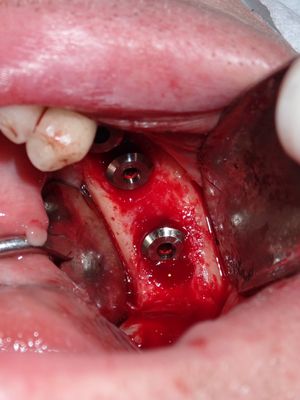

Bone loss noted, bone graft required, upon flapping, decided to place implants. Difficult case due to very strong macroglossic tongue, limited sulcular space. Short and wide implants placed, all socket/defects grafted with sticky bone from cortical allograft. membrane placed interimplant and fibrin membrane also used